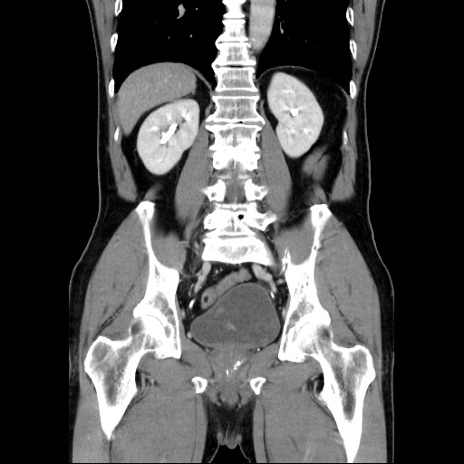

症例34(冠状断像)

【症例】60歳代 男性

【主訴】右鼠径部膨隆

【現病歴】1年程前より右鼠径部膨隆あり。自己にて還納可能だったため放置していた。3時間前より右鼠径部の脱出を認め、還納困難となり受診。

【既往歴】高血圧

【身体所見】右鼠径部に小児頭大の膨隆あり。弾性硬であり、用手還納は困難。左鼠径部にも膨隆を認める。脱出はなし。

【データ】WBC 15500、CRP 測定なし